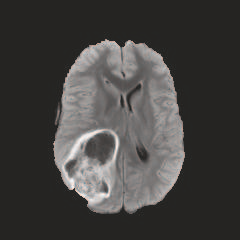

Multi-modal medical image completion has been extensively applied to alleviate the missing modality issue in a wealth of multi-modal diagnostic tasks. However, for most existing synthesis methods, their inferences of missing modalities can collapse into a deterministic mapping from the available ones, ignoring the uncertainties inherent in the cross-modal relationships. Here, we propose the Unified Multi-Modal Conditional Score-based Generative Model (UMM-CSGM) to take advantage of Score-based Generative Model (SGM) in modeling and stochastically sampling a target probability distribution, and further extend SGM to cross-modal conditional synthesis for various missing-modality configurations in a unified framework. Specifically, UMM-CSGM employs a novel multi-in multi-out Conditional Score Network (mm-CSN) to learn a comprehensive set of cross-modal conditional distributions via conditional diffusion and reverse generation in the complete modality space. In this way, the generation process can be accurately conditioned by all available information, and can fit all possible configurations of missing modalities in a single network. Experiments on BraTS19 dataset show that the UMM-CSGM can more reliably synthesize the heterogeneous enhancement and irregular area in tumor-induced lesions for any missing modalities.